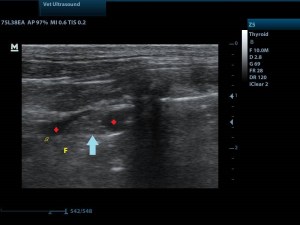

τα βέλη δείχνουν την πορεία των λοβών του πνεύμονα.

μπλε βέλος: λοβός του πνεύμονα

αστερίσκοι: υγρό ( μαύρο)